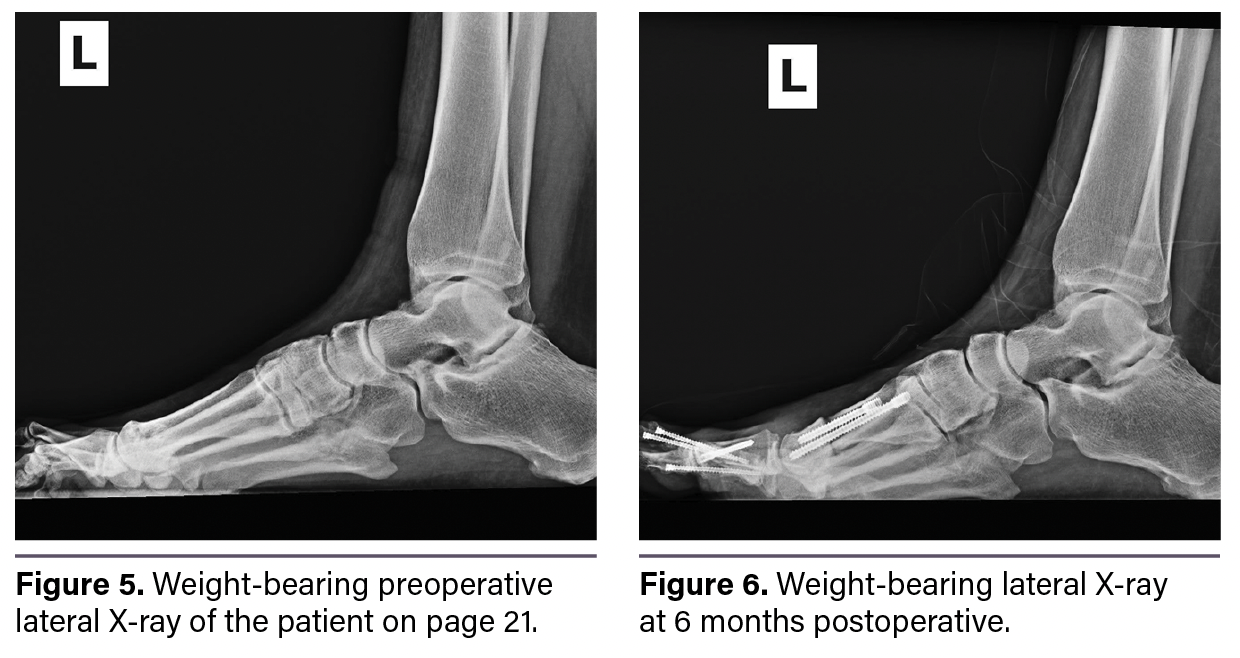

Figure 3 shows a weight-bearing preoperative dorsoplantar X-ray. Figure 4 shows the postoperative weight-bearing dorsoplantar X-ray with bone healing at 6 months. Figure 5 shows a preoperative weight-bearing lateral X-ray and Figure 6 shows a postoperative weight-bearing lateral X-ray at 6 months. The patient’s postoperative hallux angle was 17.6 degrees compared to 40.4 degrees preoperatively. The postoperative first intermetatarsal (IM) angle was 1.9 degrees with a tibial sesamoid position of 2 compared to preoperative values of 10.1 degrees and 5, respectively. The postoperative fourth–fifth IM angle was 4.2 degrees compared to 9.1 preoperatively.